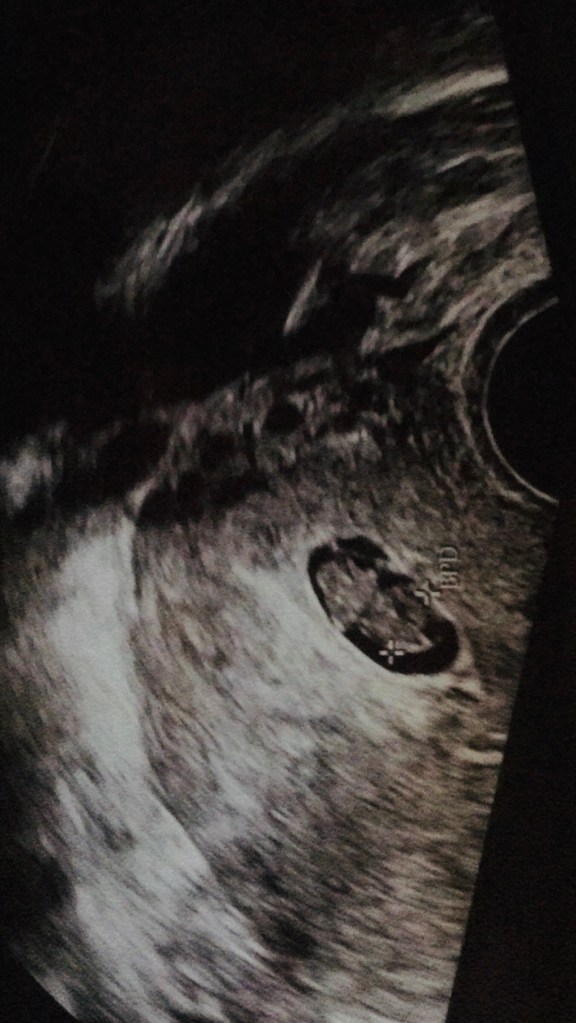

Der Ultraschall zeigte nun also das, was ich gehofft, aber nicht so ganz erwartet hätte: Ein kleines Menschlein mit Herzschlag. Die Gynäkologin äußerte sich in ihrer mir bekannten Weise dazu und ich ließ all das nicht an mich heran. Für mich bestand nun also Hoffnung und darauf wollte ich mich einlassen.